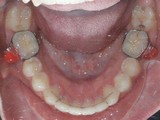

Zkřížený skus, předkus, nedostatek místa pro špičák. Léčba pomocí aparátu Hyrax a dále fixními aparáty v obou čelistech s jumping aparátem. V ústech přítomné MARA-stopy na dočasnou stabilizaci výsledku.

Před léčbou        Po léčbě

dolní pac2       dolní pac2